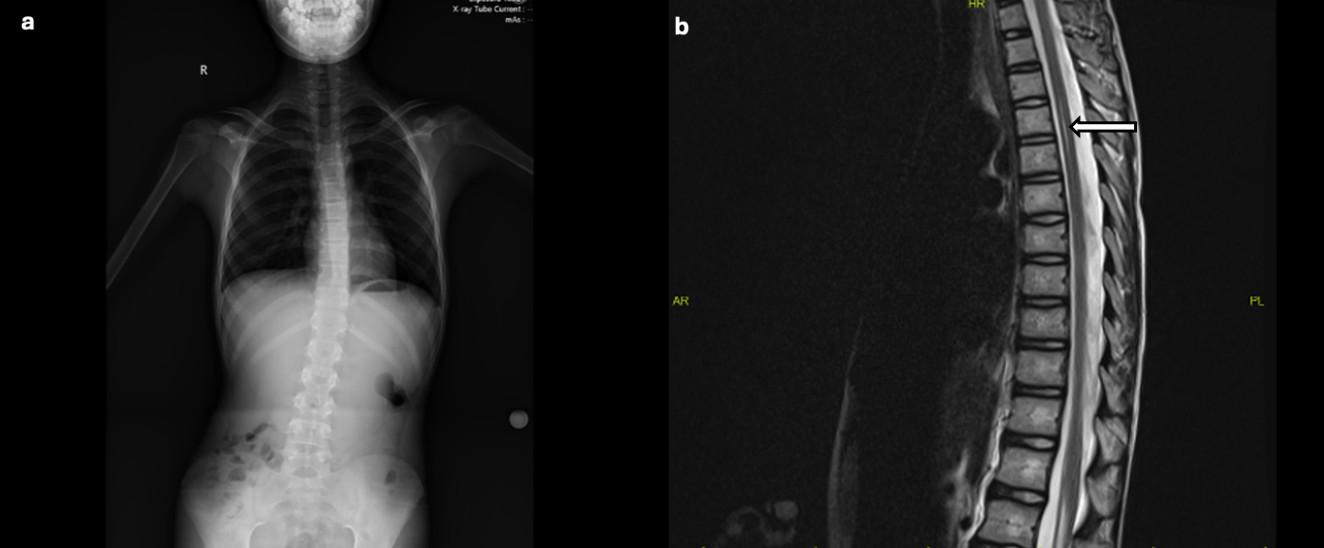

The patient, who had been previously followed by pediatric neurology, was noted to have borderline serum magnesium levels (1.7 mg/dL) approximately one year earlier, along with mildly elevated AST (51 IU/L) and ALT (45 IU/L) levels. Thyroid function tests; vitamin B12, folic acid, and 25-hydroxyvitamin D levels; carnitine-acylcarnitine analysis by tandem mass spectrometry; urinary organic acid analysis; and serum lactate, pyruvate, and ammonia levels were all within normal limits. Urinary, hepatobiliary, and suprapubic pelvic ultrasonography findings were normal. Scoliosis radiography confirmed thoracolumbar scoliosis (Fig. 1a). Brain MRI showed no abnormalities. Cervical MRI revealed loss of cervical lordosis, while thoracic MRI demonstrated a central syrinx in the spinal cord extending from the T3 to T6 levels (Fig. 1b).

Neuroimaging findings in our patient included loss of cervical lordosis and a thoracic spinal cord syrinx extending from T3 to T6. Although such findings have not been routinely reported in association with 17q12 deletion syndrome, they may represent underrecognized aspects of its broader neurodevelopmental phenotype. Existing literature has focused mainly on brain malformations. The coexistence of spinal syringomyelia in our patient therefore may reflect an underrecognized manifestation of the broader neurodevelopmental phenotype associated with 17q12 deletion syndrome. Several mechanisms may be proposed: (1) loss of neurodevelopmentally relevant genes within the deleted 17q12 interval, such as LHX1, which plays a role in neuronal patterning and differentiation; (2) altered cerebrospinal fluid dynamics due to subtle maldevelopment of the spinal canal or hindbrain structures, even in the absence of Chiari malformation; or (3) an incidental finding unrelated to the microdeletion. Given the single-case nature of this report, causality cannot be established, and further studies are required to clarify this potential association. Our case and these hypotheses highlight the potential importance of performing spinal imaging in selected patients with 17q12 deletions, especially in those with neuromotor or postural anomalies such as scoliosis.